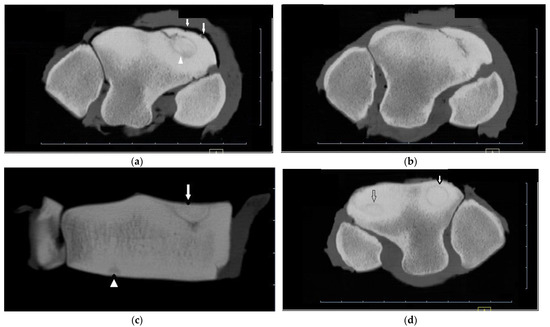

Horses ranged in age from 2 to 7 yr (mean 4.27 yr) for cases and 1 to 6 yr (mean 3.2 yr) for controls. Film radiographs (XR) were available for the fractured carpus of all 15 horses, and of the contralateral carpus in 6 horses. CT was available of the contralateral carpus of 13 horses. Fracture cases included 2 incomplete and 13 complete Fx, either frontal (n = 13) or corner (n = 2), and ranged from simple to severely comminuted. Signalment, Fx characteristics and other lesions are described in Supplementary Table S2. XR underestimated or failed to detect bone injury in all cases including comminution (nine horses) or an additional major fissure (one horse, Supplementary Figure S1), bone loss at the proximal articular surface (five horses), partial or full thickness subchondral bone lucency (SCBL) (four horses), medullary lucency in C3 (three horses) and radiocarpal bone (Cr) and or intermediate carpal bone (Ci) lesions (five horses) including osseous fragments (OF) and small, linear, triangular or rounded dorsal cortical lucencies (DCL). Incomplete C3 Fx was only detected on CT in three horses. CT confirmed Fx configuration as corner rather than sagittal in one horse. In another horse, CT identified Y- or saucer-shaped lucency within the RaF and InF of both carpi; an incomplete frontal Fx extended from the RaF lesion (Figure 1). CT confirmed complete Fx in 1 horse when incomplete Fx was diagnosed on XR. Bone injury was detected in the contralateral carpus in eight horses (8/13, 61.5%) including incomplete Fx RaF (two horses), SCBL within C3, Cr and or distal radius (diRd) (six horses) and OF Cr or Ci (three horses); and DCL were present in 2 horses.

Figure 1. CT images of the distal row of carpal bones of a 5-year-old thoroughbred gelding (post-mortem specimens). (a) Transverse CT image of the right carpus just below the proximal articular surface of the third carpal bone (C3), and (b) through the distal third of C3. (c) Dorsal CT image of the right carpus. There is a circular lucency within the radial facet (arrow head (a)) that extends as a Y-shaped lucency into the sclerotic medulla of C3 (arrow (c)), and an incomplete frontal fracture extending from this lesion to exit the dorsal cortex of C3 (a,b). Concurrent lesions include small dorsal cortical lucencies (arrows (a)) and a focal lucency within the distal subchondal bone of the intermediate facet (arrow head (c)). (d) Transverse CT image of the left carpus reveals similar circular lucencies within the radial and intermediate facets (arrows); the lucencies are saucer-shaped on dorsal and sagittal images (not shown).